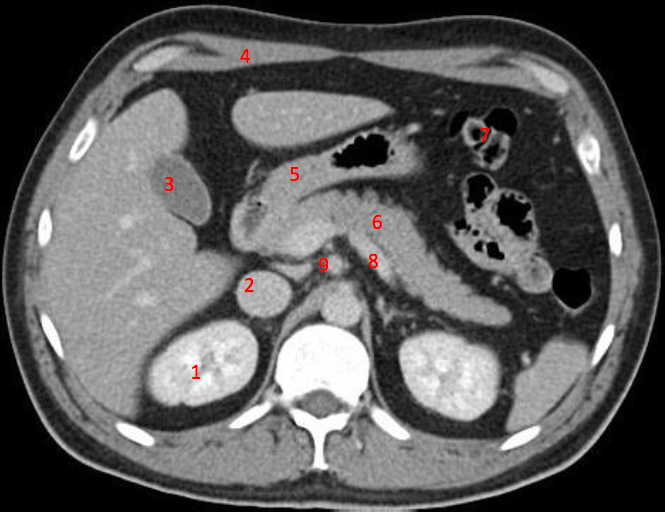

4

Number 2?

IVC

5

Number 3?

Gall bladder

13

Number 4?

Head of pancreas

14

Rt diaghragmatic crus

15

Number 7?

Bowel (probably large)

18

Number 1?

R lung

19

Rt lobe of liver

20

Number 6?

Stomach

24

Number 8?

25

Abdominal aorta

27

Spleen

28

Rt renal artery

29

Lt common iliac artery

30

Body of pancreas

31

Number 5?

32

Portal vein

36

Superior mesenteric artery

38

Splenic vein

46

Lt renal vein

47

Number 10?

Rt kidney

48

Duodendum

49

Aorta

52

Traumatic laceration of Lt kidney

53

Lt erectae spinae muscle